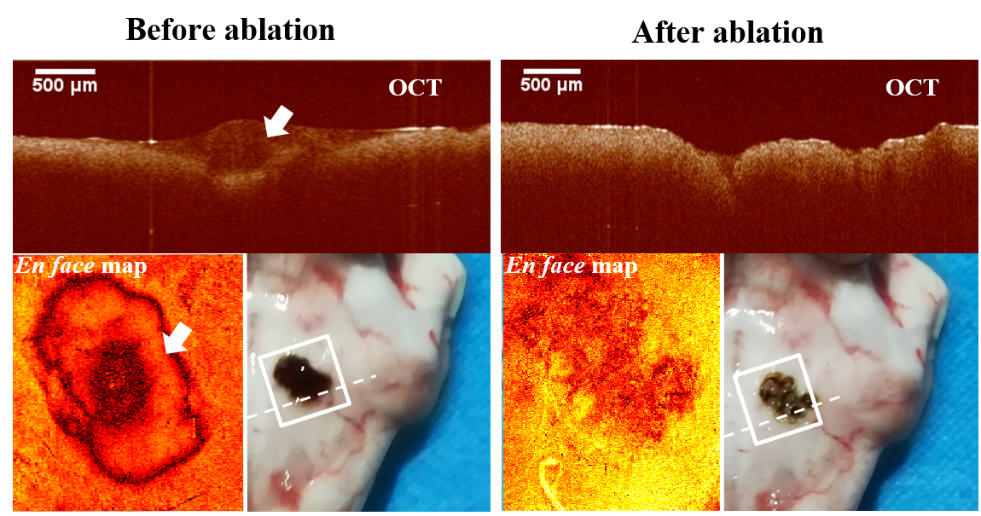

OCT引导激光消融前后肿瘤区域(白色箭头指向肿瘤)

本论文针对光学相干断层扫描(optical coherence tomography,OCT)图像引导激光消融难以实现术中实时成像和治疗有效结合的问题,提出了基于双轴的微机电振镜实现OCT系统与高功率消融激光的非共光路结合的方法。该方法能够实现OCT成像区域与消融光斑的精准匹配,为图像闭环反馈下实时自动化的肿瘤消融提供了新的解决方案。该方法通过系统搭建和离体动物实验验证了其可行性,未来通过内窥式结构设计能够实现在微创手术中精准高效的诊疗结合。